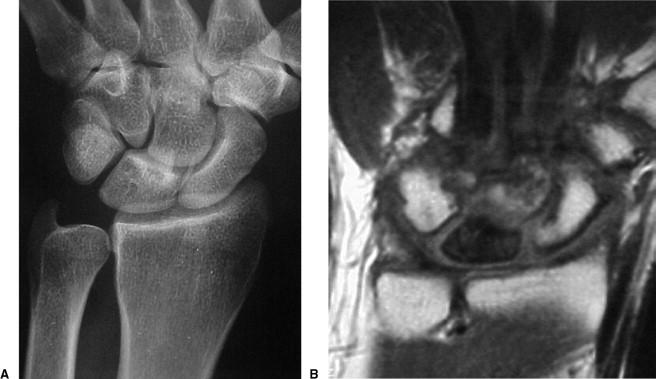

Lunate 의 sclerosis가 발견되면 Stage II 이며 Joint leveling 이 핵심입니다. ulna 변위가 중립 혹은 양성인 경우에는 radial wedge osteotomy나 그 외의 치료를 시행해 볼 수 있습니다.

Stage III 부터는 주상골도 영향을 받기 시작하며 회전을 하거나(IIIA, cortical ring 관찰가능), carpal height 가 줄어드는 것을 확인할 수 있습니다. (IIIB), IIIA 까지는 II와 치료를 거의 동일하게 하지만, IIIB 부터는 Proximal row carpectomy 나 STT, SC fusion 등을 시행해 볼 수 있습니다.